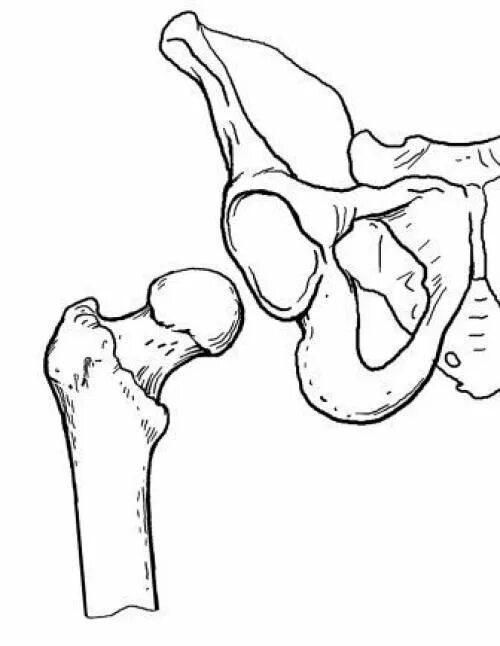

Горяев тазобедренного сустава